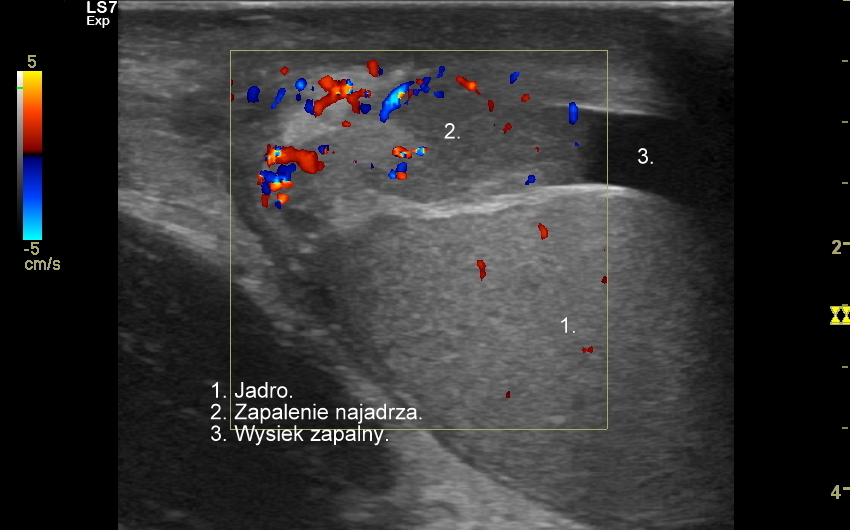

Najczęstsze choroby w obrębie moszny obejmują żylaki powrózka nasiennego, zapalenia jąder i najądrzy, wodniaki jądra, skręty szypuły jądra bądź przydatków jądra, torbiele najądrzy, nowotwory i raki jąder. Niezależnie od powyższego u chłopców spotyka się wnętrostwo, czyli niepełne zstąpienie jądra do moszny, które to może pozostać w jamie brzusznej lub pachwinie, a także ektopię jąder, czyli ich zabłąkane położenie (np. w okolicy krocza).

USG moszny i kanału pachwinowego jest podstawową metodą obrazowania jąder, najądrzy, powrózka nasiennego, w tym nasieniowodu oraz towarzyszących im naczyń żylnych i tętniczych. Badanie USG przeprowadzić należy w przypadku wystąpienia bólu i obrzęku jąder, pojawienia się macalnego guzka w obrębie moszny, podejrzenia skrętu lub zapalenia jądra, żylaków powrózka nasiennego, w ramach oceny dojrzewania płciowego chłopców. Kanał pachwinowy bada się także w sytuacji podejrzenia wnętrostwa, przepukliny pachwinowej, w celu oceny węzłów chłonnych, a także nasieniowodu w diagnostyce niepłodności męskiej.

Mosznę bada się aparatem USG wyposażonym w dedykowaną sondę o wysokiej rozdzielczości przeznaczoną do oceny jąder i drobnych struktur moszny, koniecznie z zastosowaniem trybów dopplerowskich, takich jak Doppler kodowany kolorem, Doppler spektralny i obrazowanie mikrounaczynienia. Dopełnieniem badania USG jąder jest użycie w stosownych przypadkach trybu elastografii oraz trybu USG z kontrastem (CEUS). Lekarzem, który pierwszy we Wrocławiu i na Dolnym Śląsku przeprowadził badanie CEUS jąder jest dr Tomasz Szczepański.